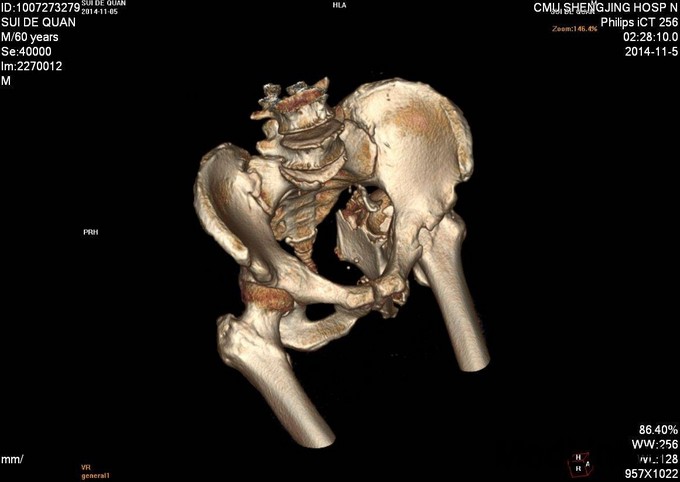

1.患者老年男性,以“车祸左髋部疼痛活动受限3天”为主诉入院。 2.现病史:患者自述于2014-11-04日晚下午7点发生机动车肇事,伤后患者急救车送往孤山二院,诊断为左髋臼骨折,当地医院未经任何治疗。急来中国医科大学附属盛京医院第五骨科创伤骨科治疗。我科以“左髋臼骨折”为主要诊断收入院。今来我院就诊,患者病来一般状态可,生命体征平稳,无发烧无发热,饮食睡眠可。

专科查体:患者平车入病房,左腿内收内旋屈曲畸形,左髋部压痛(+),叩击痛(+),骨盆分离试验阳性,活动受限,双下肢感觉未见异常,活动可,双侧足背动脉搏动可触及,双侧足趾活动灵活。

入院后急诊行左髋关节脱位复位术,左胫骨结节骨骼牵引术。术后牵引7公斤,完善相关检查后,全麻下行左髋臼骨折切开复位内固定术。术后患者生命体征平稳,卧床。术后14天拆线后出院,回当地医院继续治疗。